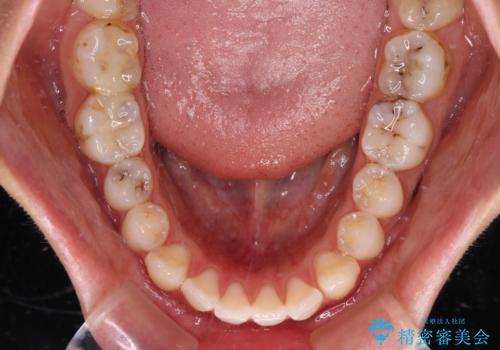

- 前歯のデコボコと口元の突出感を気にして来院された患者様です。

口元の突出感が認められ、更には左右で異なる咬合状態であったため、下顎右側は第二小臼歯を、左側は第一小臼歯を抜去することでバランスを取るような治療計画としました。

下顎の抜歯位置を左右で変えることで、最終的に上下正中をほぼ一致させることができました。